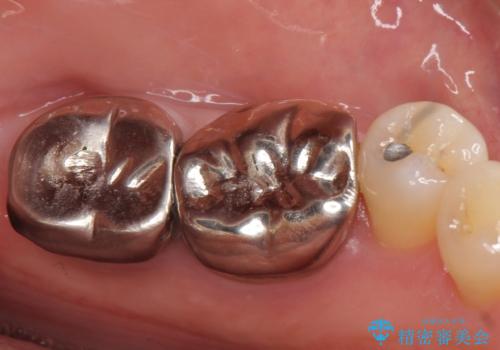

- 左下の奥歯が激しく痛むので診て欲しいといらっしゃった方の症例です。

左下7番目の歯に根尖病変を認めたため、再根管治療を行いました。

症状の消失を確認後、オールセラミッククラウンによる補綴を行いました。